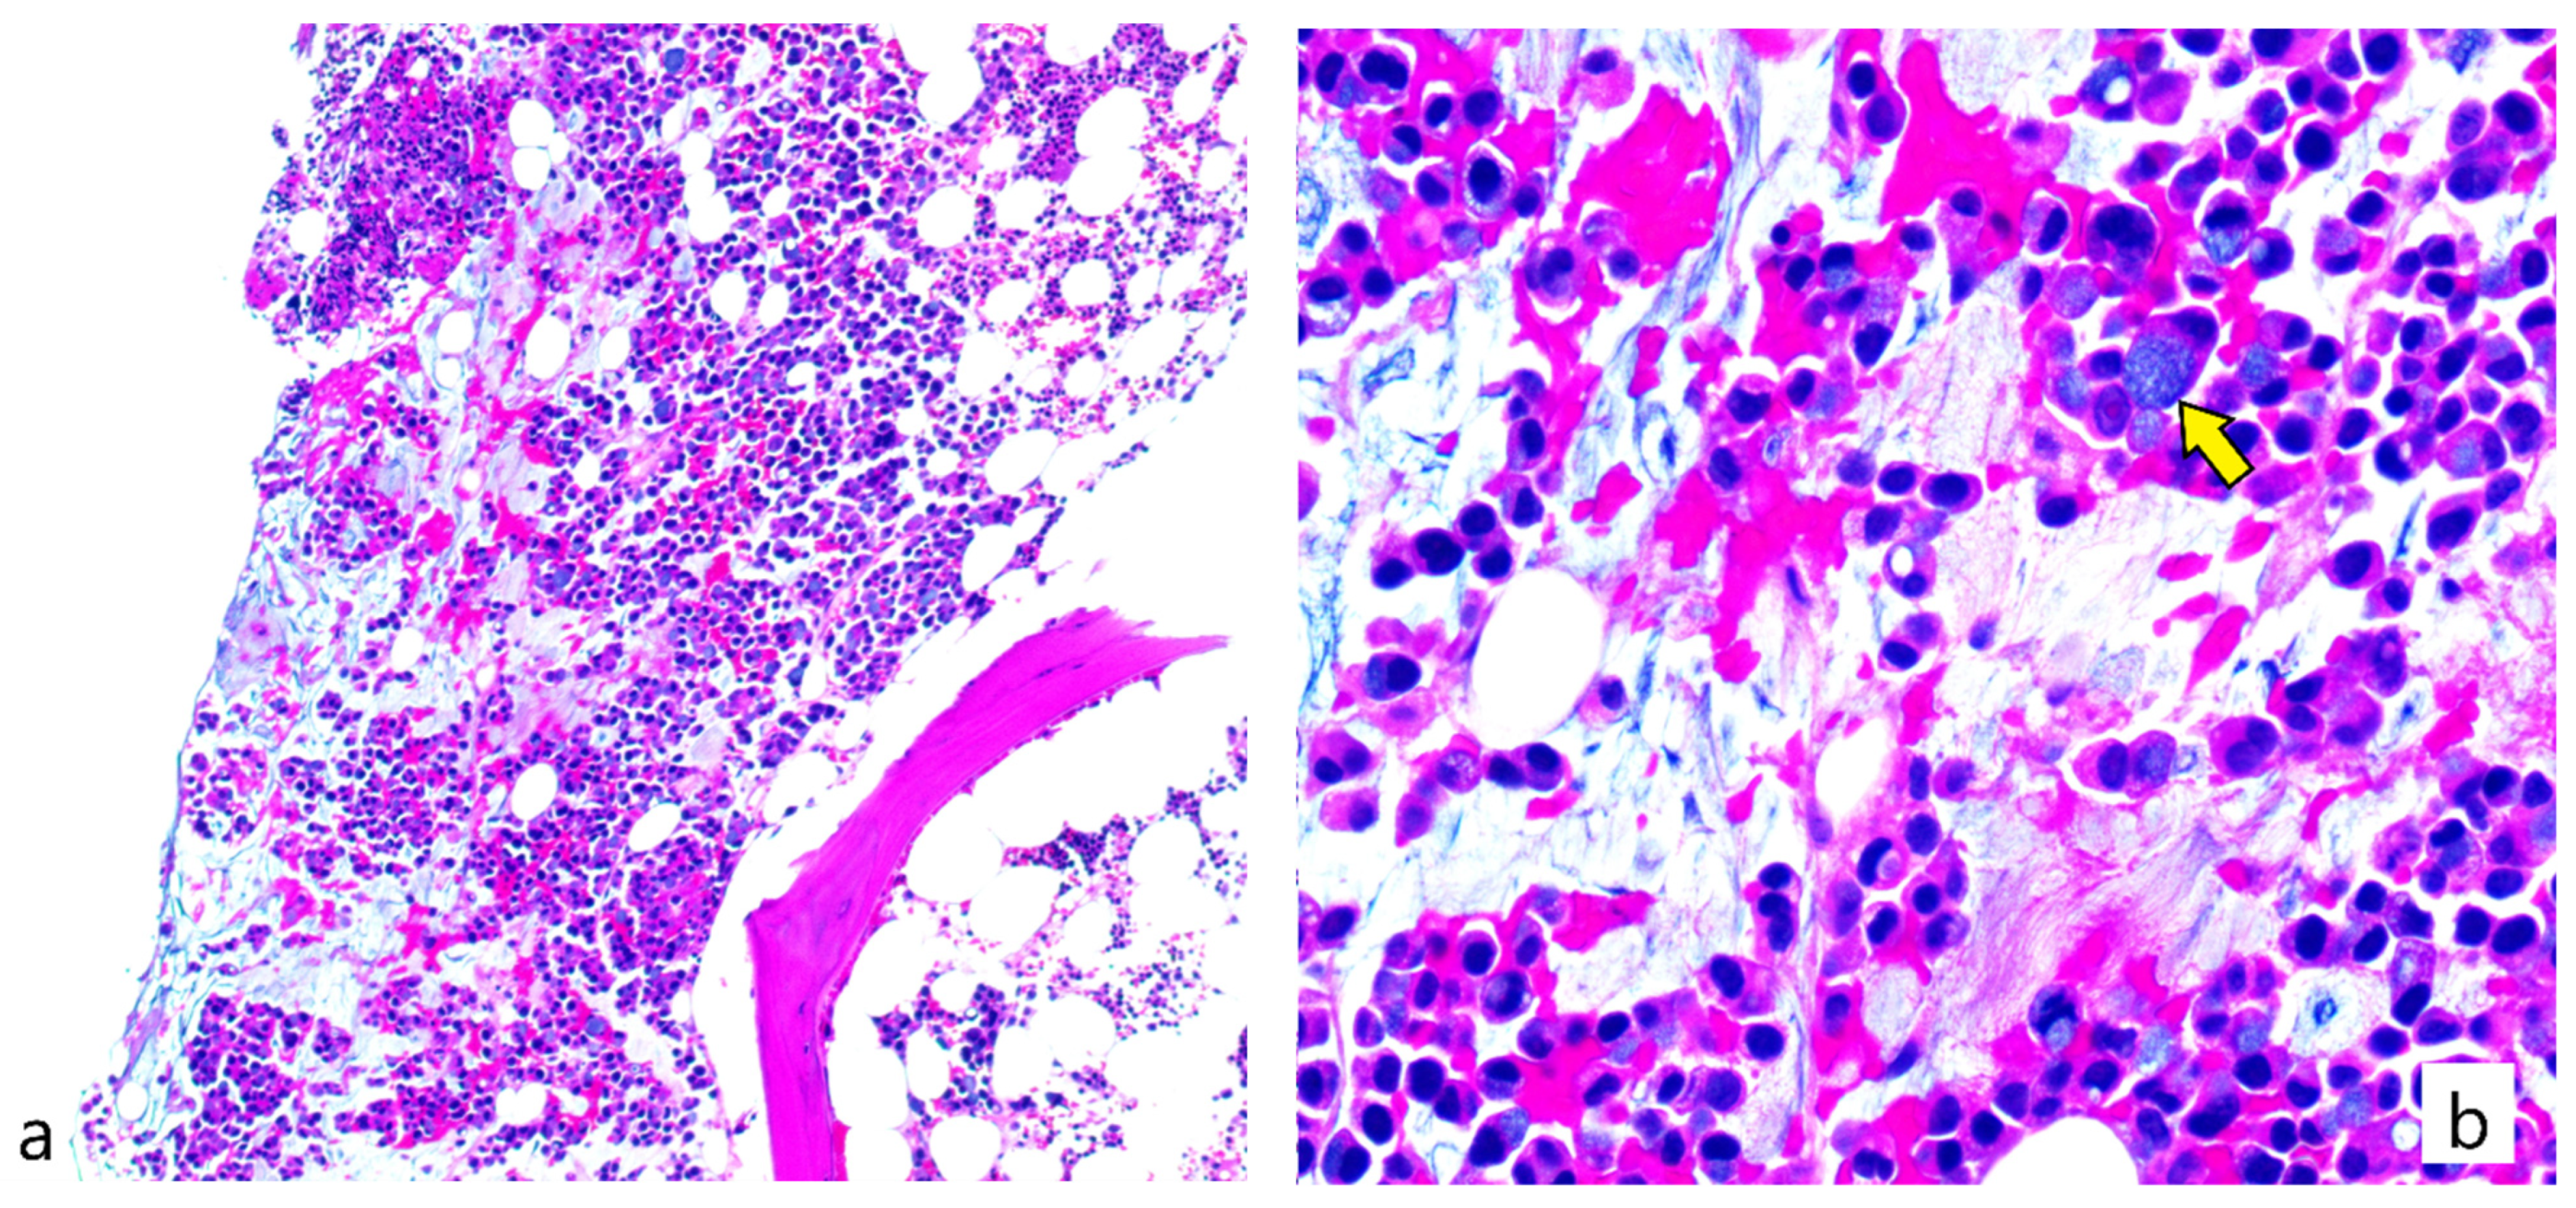

2. Case